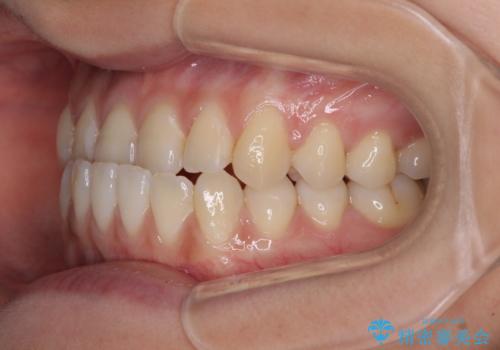

前歯のクロスバイトを治したい ワイヤー装置による矯正治療

- 前歯の反対咬合を気にして来院された患者様です。

マウスピース矯正も提案しましたが、しっかりと使用する自信がないとのことで、ワイヤー装置により矯正治療を行うこととしました。

クロスバイト改善まではスムーズに進みましたが、その後は強い舌の突出癖によりオープンバイトの期間が長く続きました。

舌のトレーニングをしっかりと実施してもらい、何とか仕上げることができました。